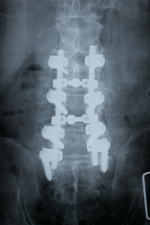

後側方固定術 後側方固定術

60歳台の男性

主訴:両下肢のシビレ。下肢筋力低下のため歩行

時にふらつく。

MRI :第3腰椎〜第5腰椎の広範囲で脊柱管に

狭窄が認められた。(がっちりした男性

にときどき見られます。)

診断:腰部脊柱管狭窄症(広範囲で狭窄がみら

れる場合、このような症状が見られます。)

手術:後側方固定術(右の写真では第3腰椎から

仙骨の範囲で固定しています。)